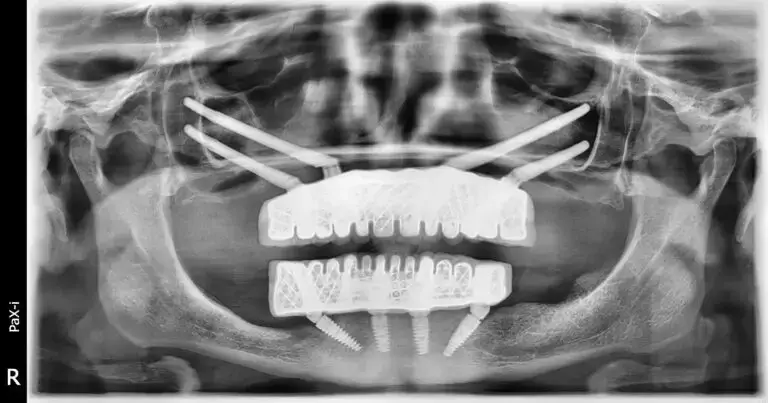

Uiteindelijk leidde haar vastberadenheid haar naar ZAGA Center Bursa, een van Smile24h’s Expert Clinics in Turkije, waar ze Dr. Kerem Turgut Atasoy ontmoette, een specialist met uitgebreide ervaring in het behandelen van complexe gevallen van maxillaire atrofie met behulp van geavanceerde technieken, waaronder zygomatische implantaten. Voor het eerst in jaren voelde Melek zich echt gehoord en begrepen. Dr. Atasoy voerde een grondige klinische evaluatie uit, inclusief 3D-beeldvorming en een gedetailleerde functionele en esthetische beoordeling.

Een moderne, minimaal invasieve oplossing: zygomatische en all-on-4 implantaten

In plaats van invasieve bottransplantatieprocedures voor te stellen die lange genezingstijden en onzekere resultaten zouden vereisen, stelde Dr. Atasoy een geavanceerde oplossing voor, op maat gemaakt voor Melek’s behoeften:

- Vier zygomatische implantaten in de bovenkaak om een volledige prothese direct in het jukbeen te verankeren, waardoor de noodzaak voor bottransplantatie wordt omzeild.

- Een All-on-4 implantaatoplossing in de onderkaak om een stabiele, vaste basis te bieden met behulp van vier strategisch geplaatste implantaten.

Melek onderging de procedure onder algehele verdoving, wat haar comfort gedurende de hele procedure verzekerde. In één operatie werden

Drie maanden later was het tijd voor de laatste stap: levering van haar vaste, slimme hybride keramische, geschroefd bevestigde prothesen bij ZAGA Center Bursa, Smile24h Expert Kliniek. Deze zeer duurzame en esthetisch op maat gemaakte tanden boden Melek een stabiele, langdurige oplossing — een die natuurlijk oogde en aanvoelde.